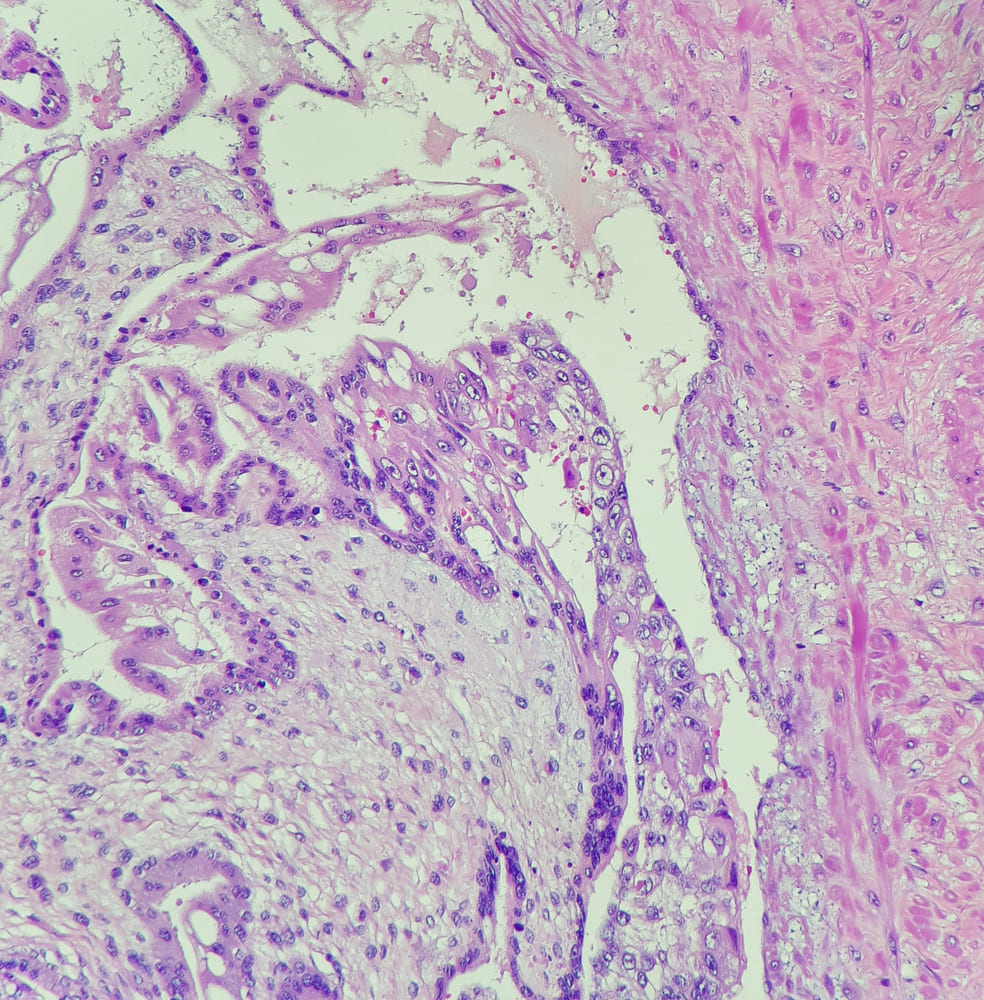

Медицина и диагностика: Инвазивный пузырный занос на УЗИ